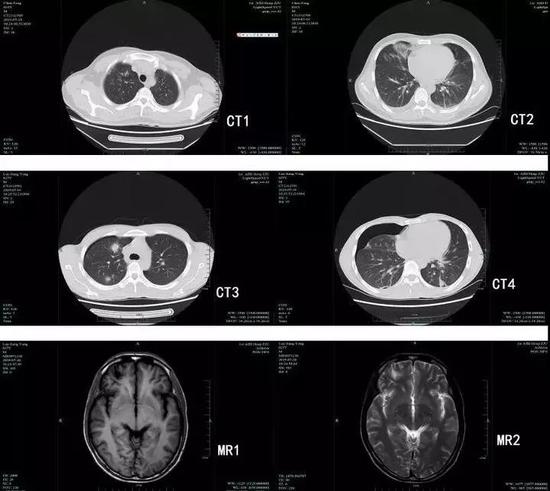

肺吸蟲感染后的肺部團塊影和顱內軟化灶

果然,經過寄生蟲檢測,兩人均為衛氏肺吸蟲抗體陽性,均在腹部和肺部發現肺吸蟲,駱某更是在腦子里發現肺吸蟲囊性灶,比較嚴重。幸好兩人發現及時,并且就醫及時,經過藥物治療后康復出院,沒有留下后遺癥。